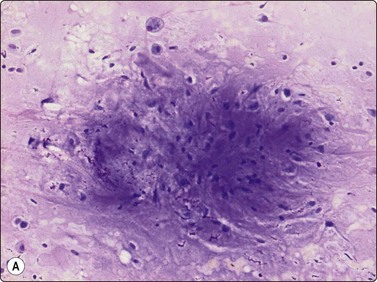

Proliferative myositis and fasciitis are less frequent pseudosarcomatous processes but are important with regard to the rapid growth (common to all these lesions) and their occurrence in children. Their cytomorphology is similar to that of nodular fasciitis although the myxoid matrix is less prominent and the ganglion cell-like cells are often numerous with very prominent nucleoli (Fig. 15.3). In proliferative myositis regenerating multinucleated muscle fibers are commonly present (Fig. 15.4). An important clinical sign is that these lesions, especially nodular fasciitis, can disappear spontaneously or diminish substantially in size within 3–4 weeks after needling.15,16 Another lesion which cytologically demonstrates prominent reactive cellular changes is pseudomalignant myositis ossificans (PMO). PMO is a rapidly growing lesion (intramuscular or subcutaneous), smears showing a mixture of proliferating fibroblasts/myofibroblasts, osteoblasts with prominent reactive changes and multinucleated giant cells of osteoclastic type (Fig. 15.5). In PMO an ossification in a zonal pattern is a typical find within 3–4 weeks and, according to our experience, spontaneous resolution is common. The cytomorphology in our series of five cases17 is similar to that described by Dodd et al.13

Fig. 15.3 Proliferative fasciitis

Ganglion cell-like cells are often numerous with very prominent nucleoli (H&E, HP).